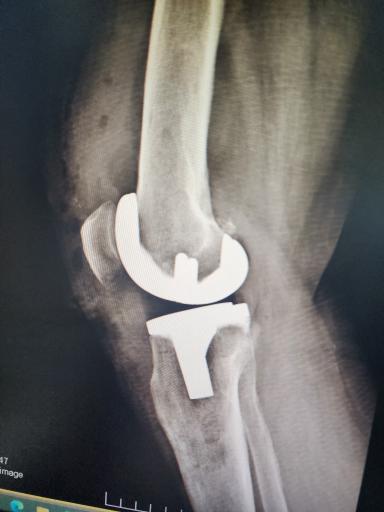

تعویض مفصل

درود پدرم خدمت ایشان عمل زانو انجام دادن خداروشکر راضی ایم

دکتر جعفری تعویض مفصل واسه مادرم انجام دادن خیلی راضی هستیم

تصاویر دکتر حامد جعفری

دکتر حامد جعفری با هفده سال سابقه درخشان در جراحی ارتوپدی ، جراحی زانو ، شکستگی‌ها